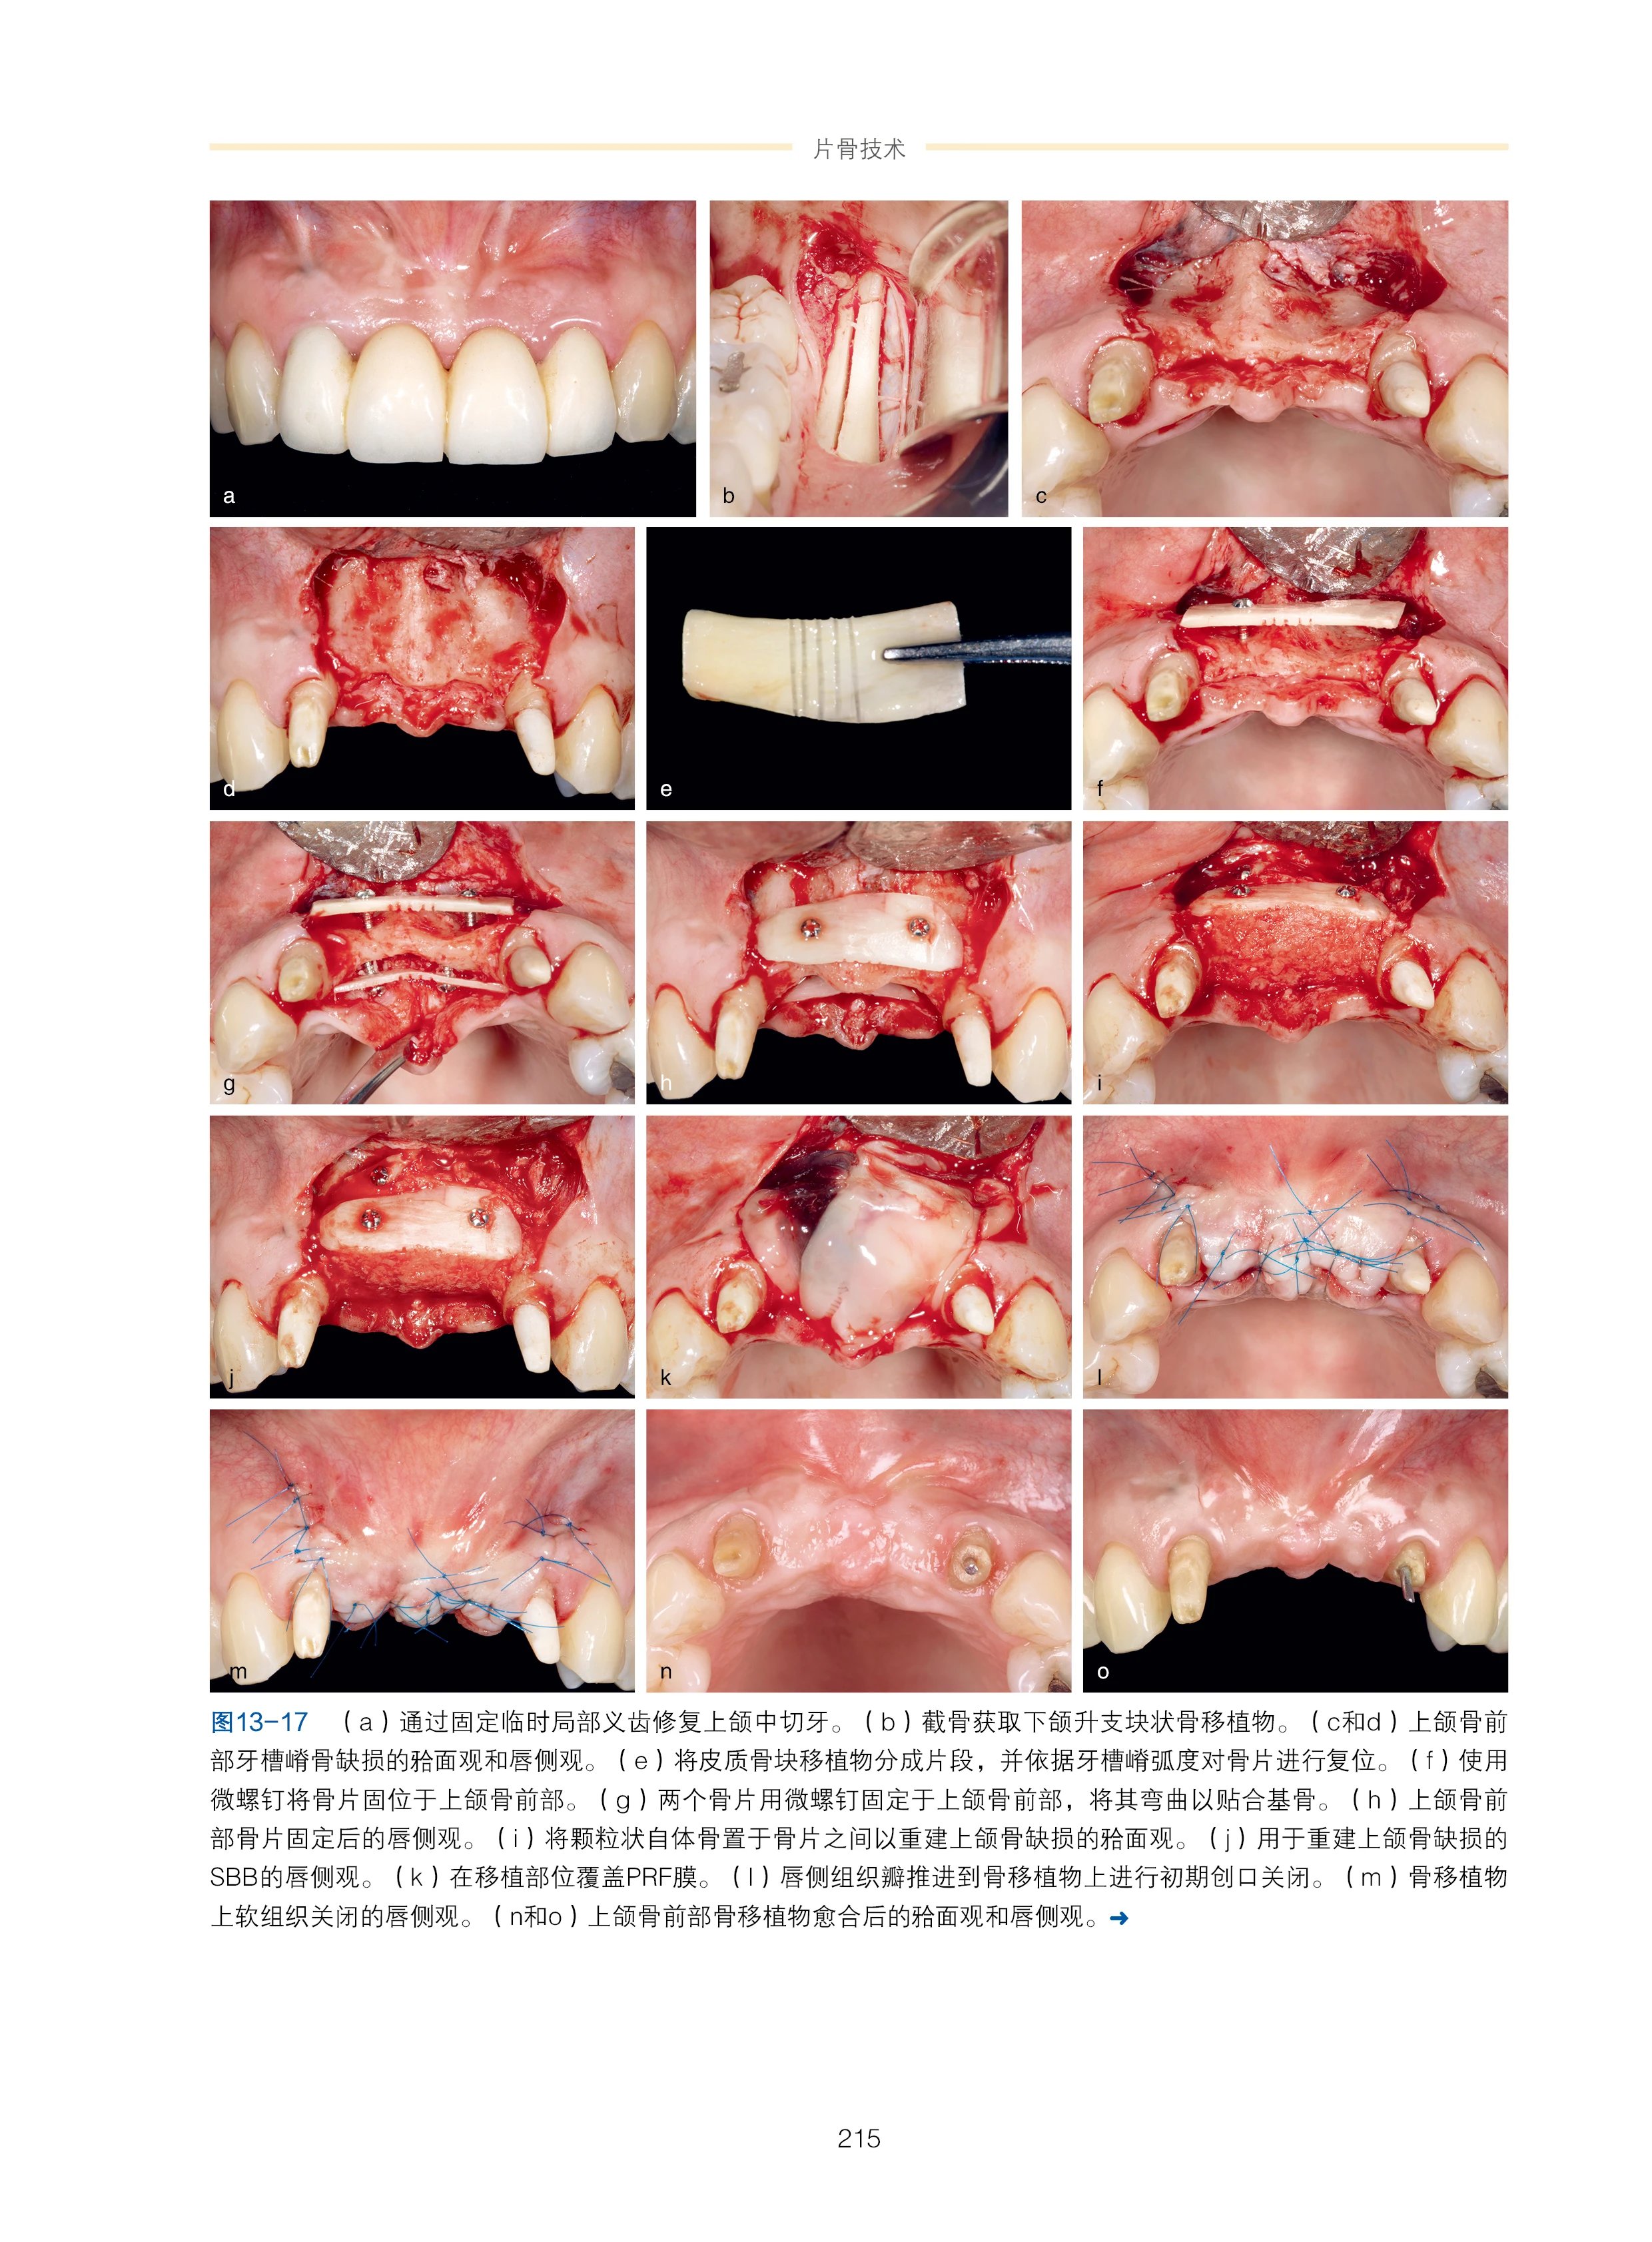

精彩页